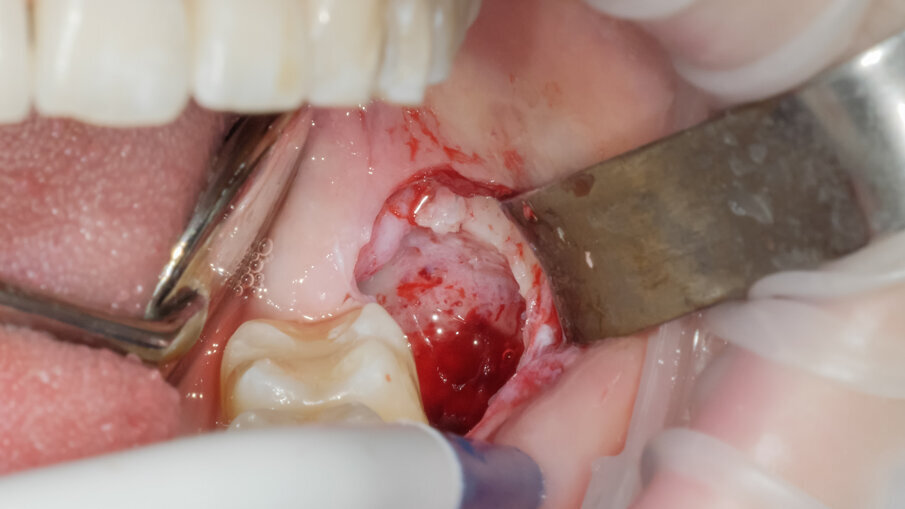

La scelta condivisa è quella di utilizzare la tecnologia piezolettrica per le fasi di odontotomia, solo nelle zone di difficile accesso o in prossimità di strutture anatomiche a rischio come il nervo alveolare inferiore. Per la fase di lussazione si è applicato il protocollo descritto da Fontanella utilizzando il nuovo inserto EXL1 (Figg. 6, 7). Questo inserto insieme agli altri due inserti lussativi (EXL2, EXL3) hanno la particolarità di sfruttare l’impulso piezoelettrico associato al movimento lussativo dell’inserto montato sul manipolo. La cavità residua è stata gestita rimuovendo i residui di sacco follicolare e detergendo il sito post estrattivo sfruttando l’effetto cavitazionale della tecnologia piezoelettirca (Fig. 8). Il lembo riposizionato è stato suturato con chiusura per prima intenzione con punti singoli riassorbibili 4/0 (Fig. 9). Al controllo post operatorio la ferita presentava una guarigione nella norma, e la paziente riferiva un post operatorio senza particolare gonfiore e con assunzione di antidolorifico solo nel primo giorno post chirurgico